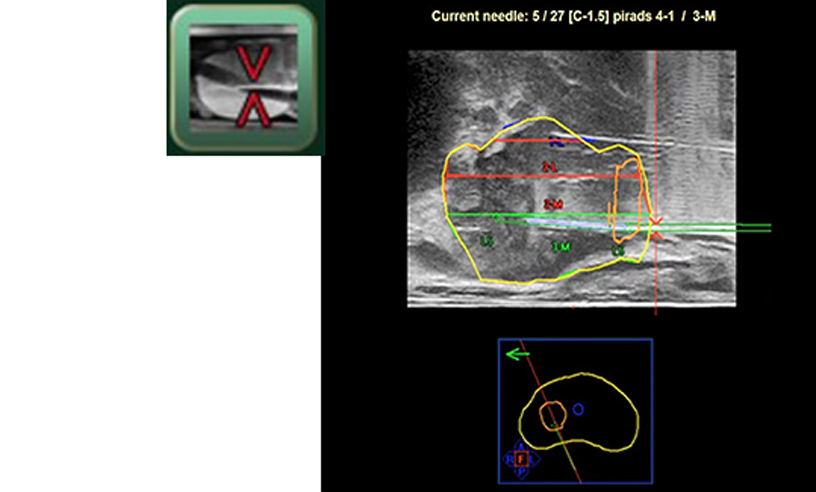

- Needle planning by easy mouse operation

- An automatic needle placement for efficient systematic biopsy planning

- Needle location guiding by Navigation Window

- Display of needle guidelines and template coordinates

- Adding new biopsy locations in real time

- Possible to correct and record the position and angle of the actual needle.